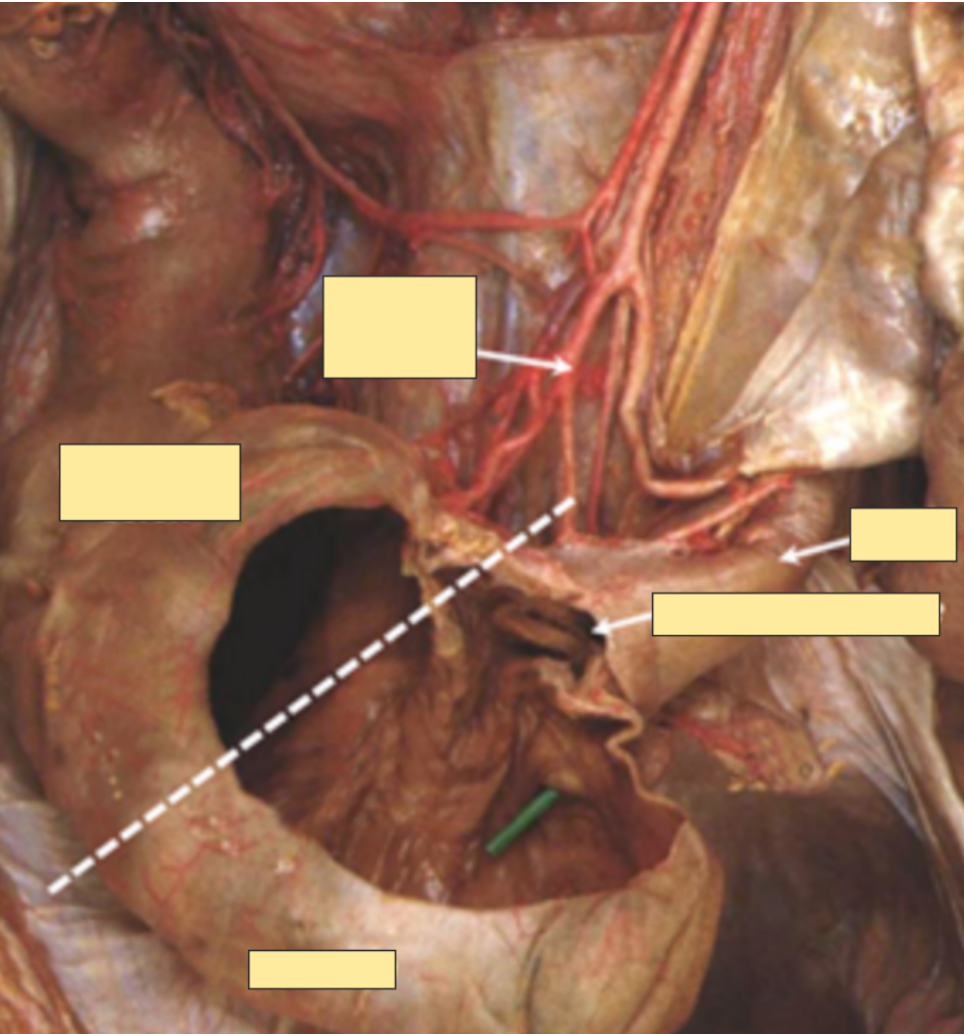

what vessel provides the caecum?

A

ileocolic artery –> branch of SMA

21

Q

What junction is found in the caecum?

What supplies the caecum?

Where does this artery come from?

Ileocaecal junction

Ileocolic artery which is a branch of the superior mesenteric artery